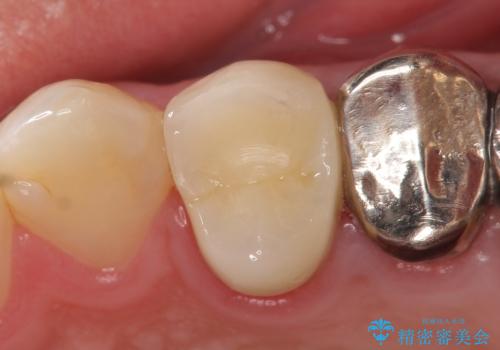

- 歯茎にできものが出来てなかなか治らないので診て欲しいといらっしゃった方の症例です。

診査の結果、左上4番目の歯の神経が死んでおり、根尖に膿が溜まっていることが原因とわかりました。

そのため左上4番目の歯は根管治療を行い、歯茎の膿の出口の消失を確認後、オールセラミッククラウンによる補綴を行いました。